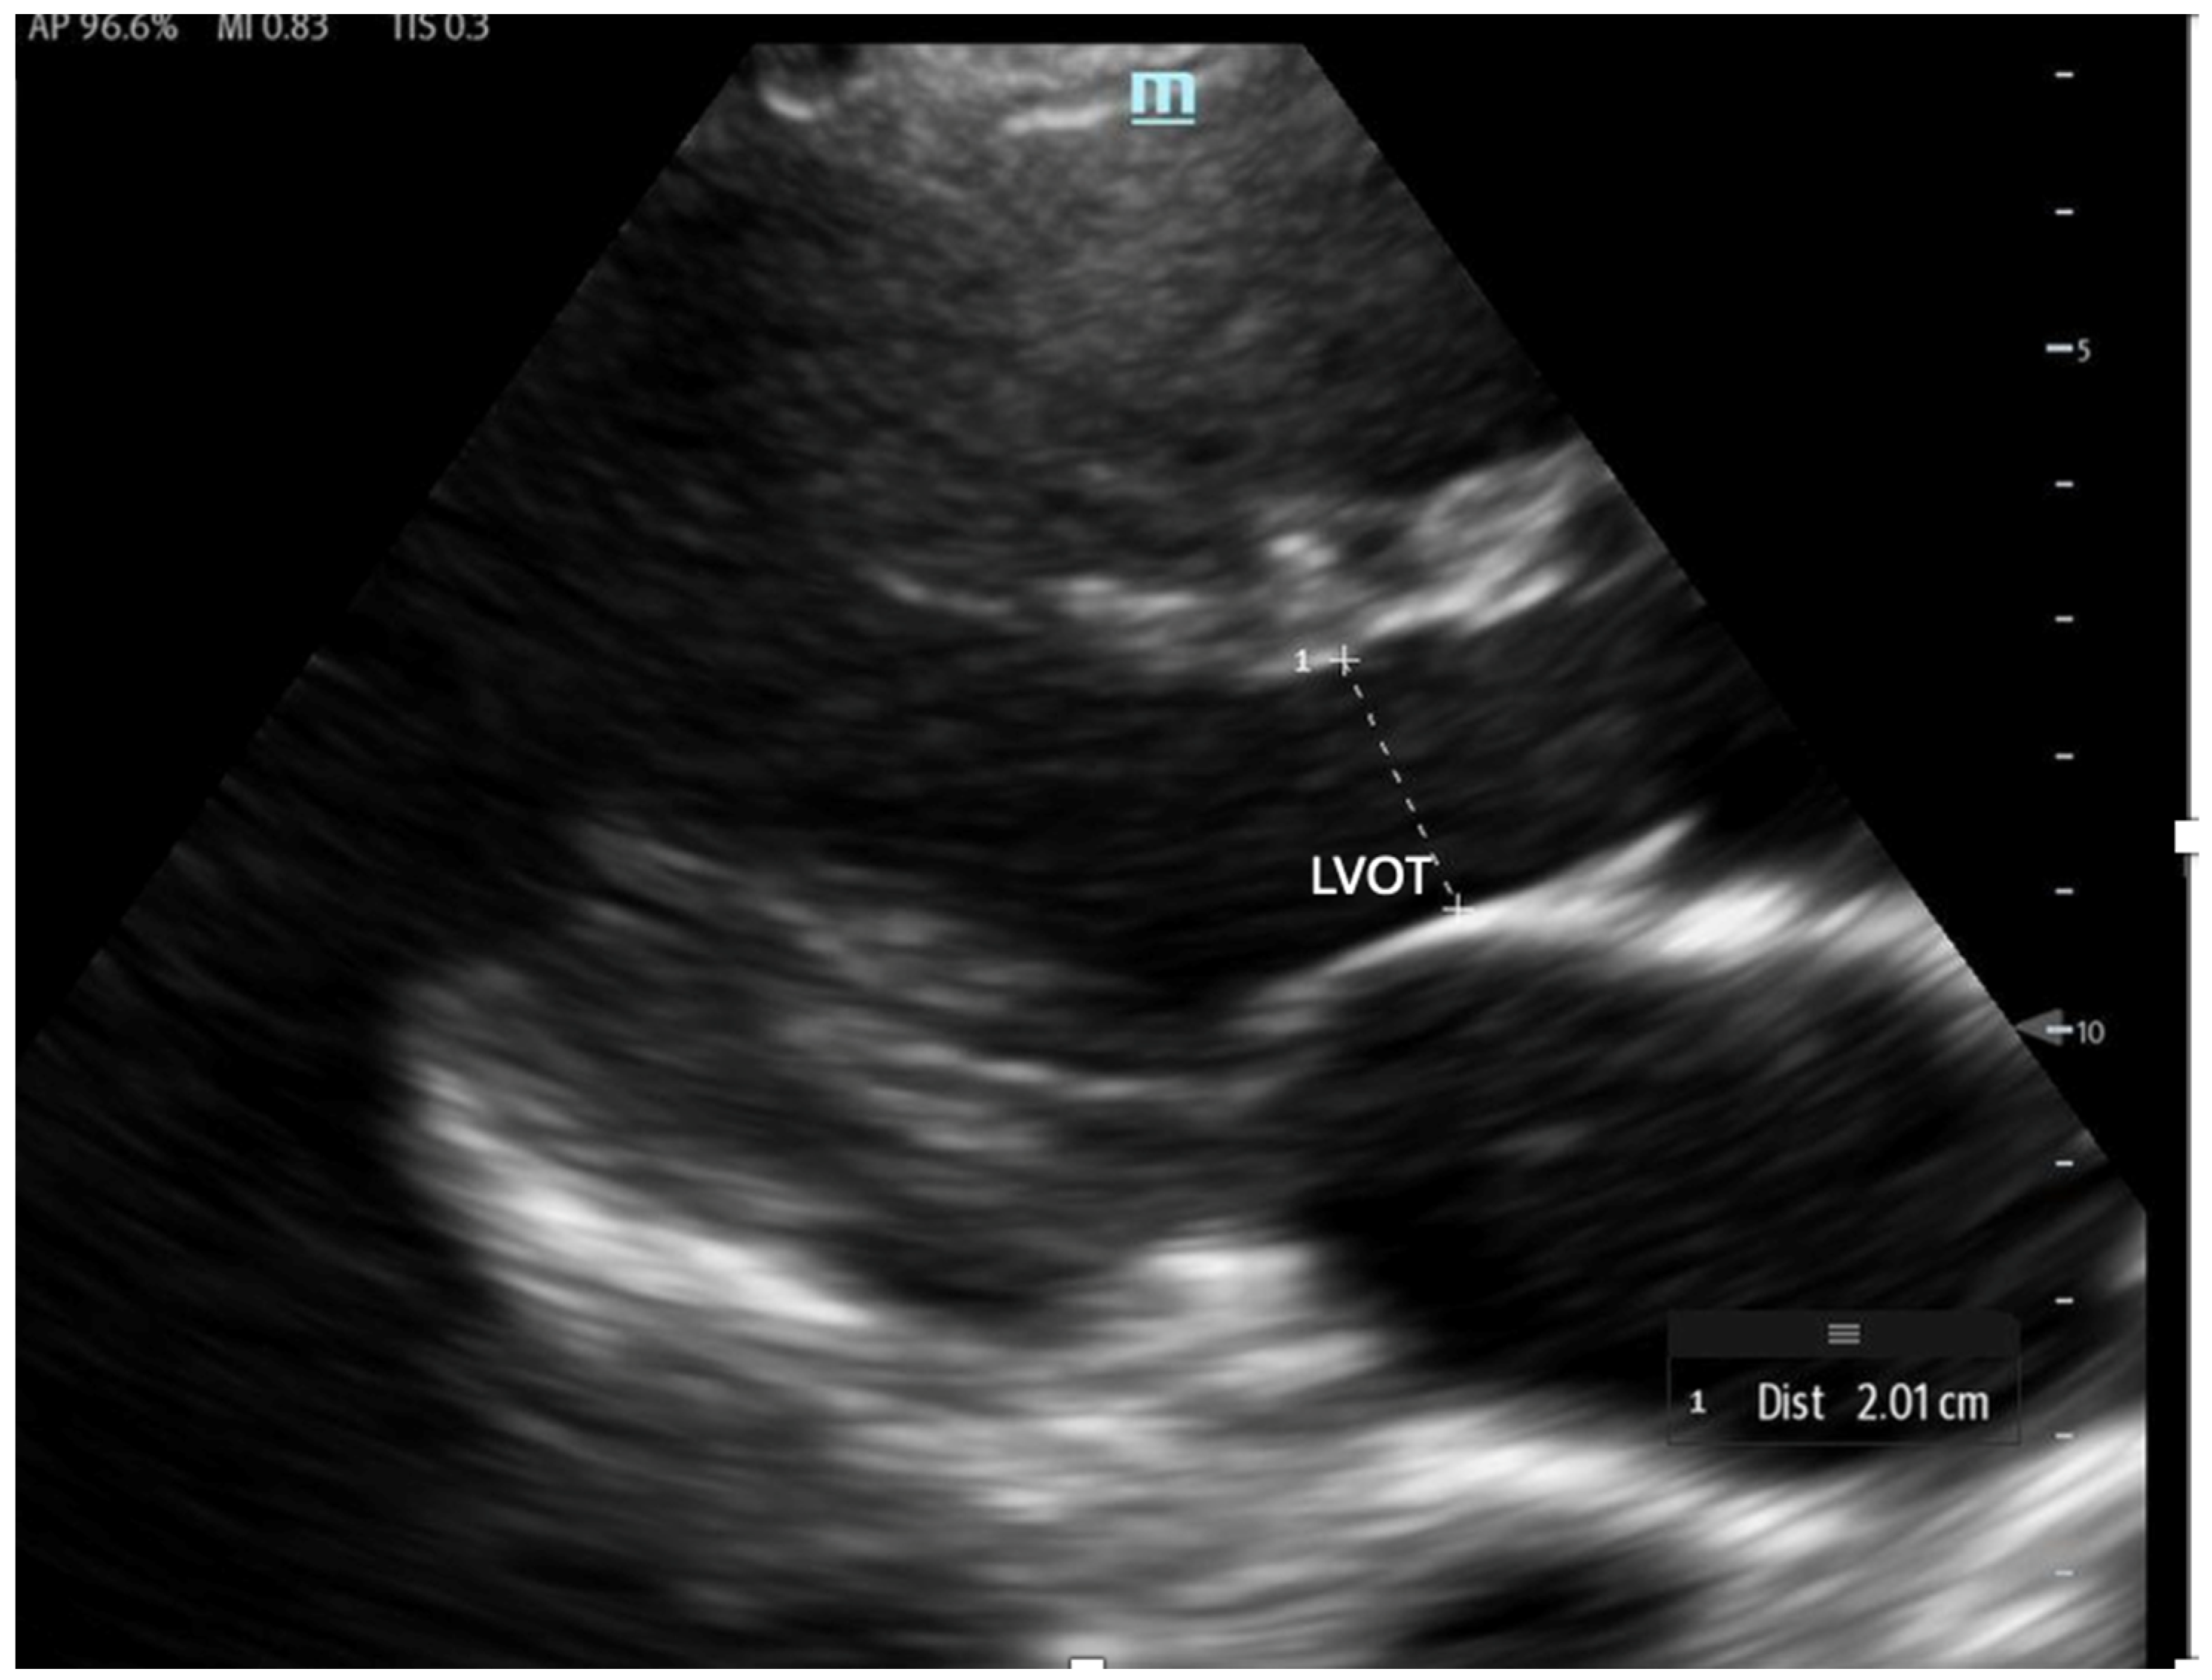

To estimate SV and CO, ultrasound requires two key measurements: the LVOT diameter and the LVOT-VTI. Cardiac output can also be indexed to body surface area to calculate the cardiac index (CI), further enhancing the hemodynamic assessment.

The LVOT diameter is measured in the PLAX view, focusing on the LVOT and aortic valve when maximally open during mid-systole (Figure 12). The measurement is taken at the base of the aortic valve, and the area is calculated using the formula:

Figure 12.

The LVOT diameter measured below the opening of the aortic valve in a zoomed-in parasternal long axis to be incorporated into the LVOT area formula.